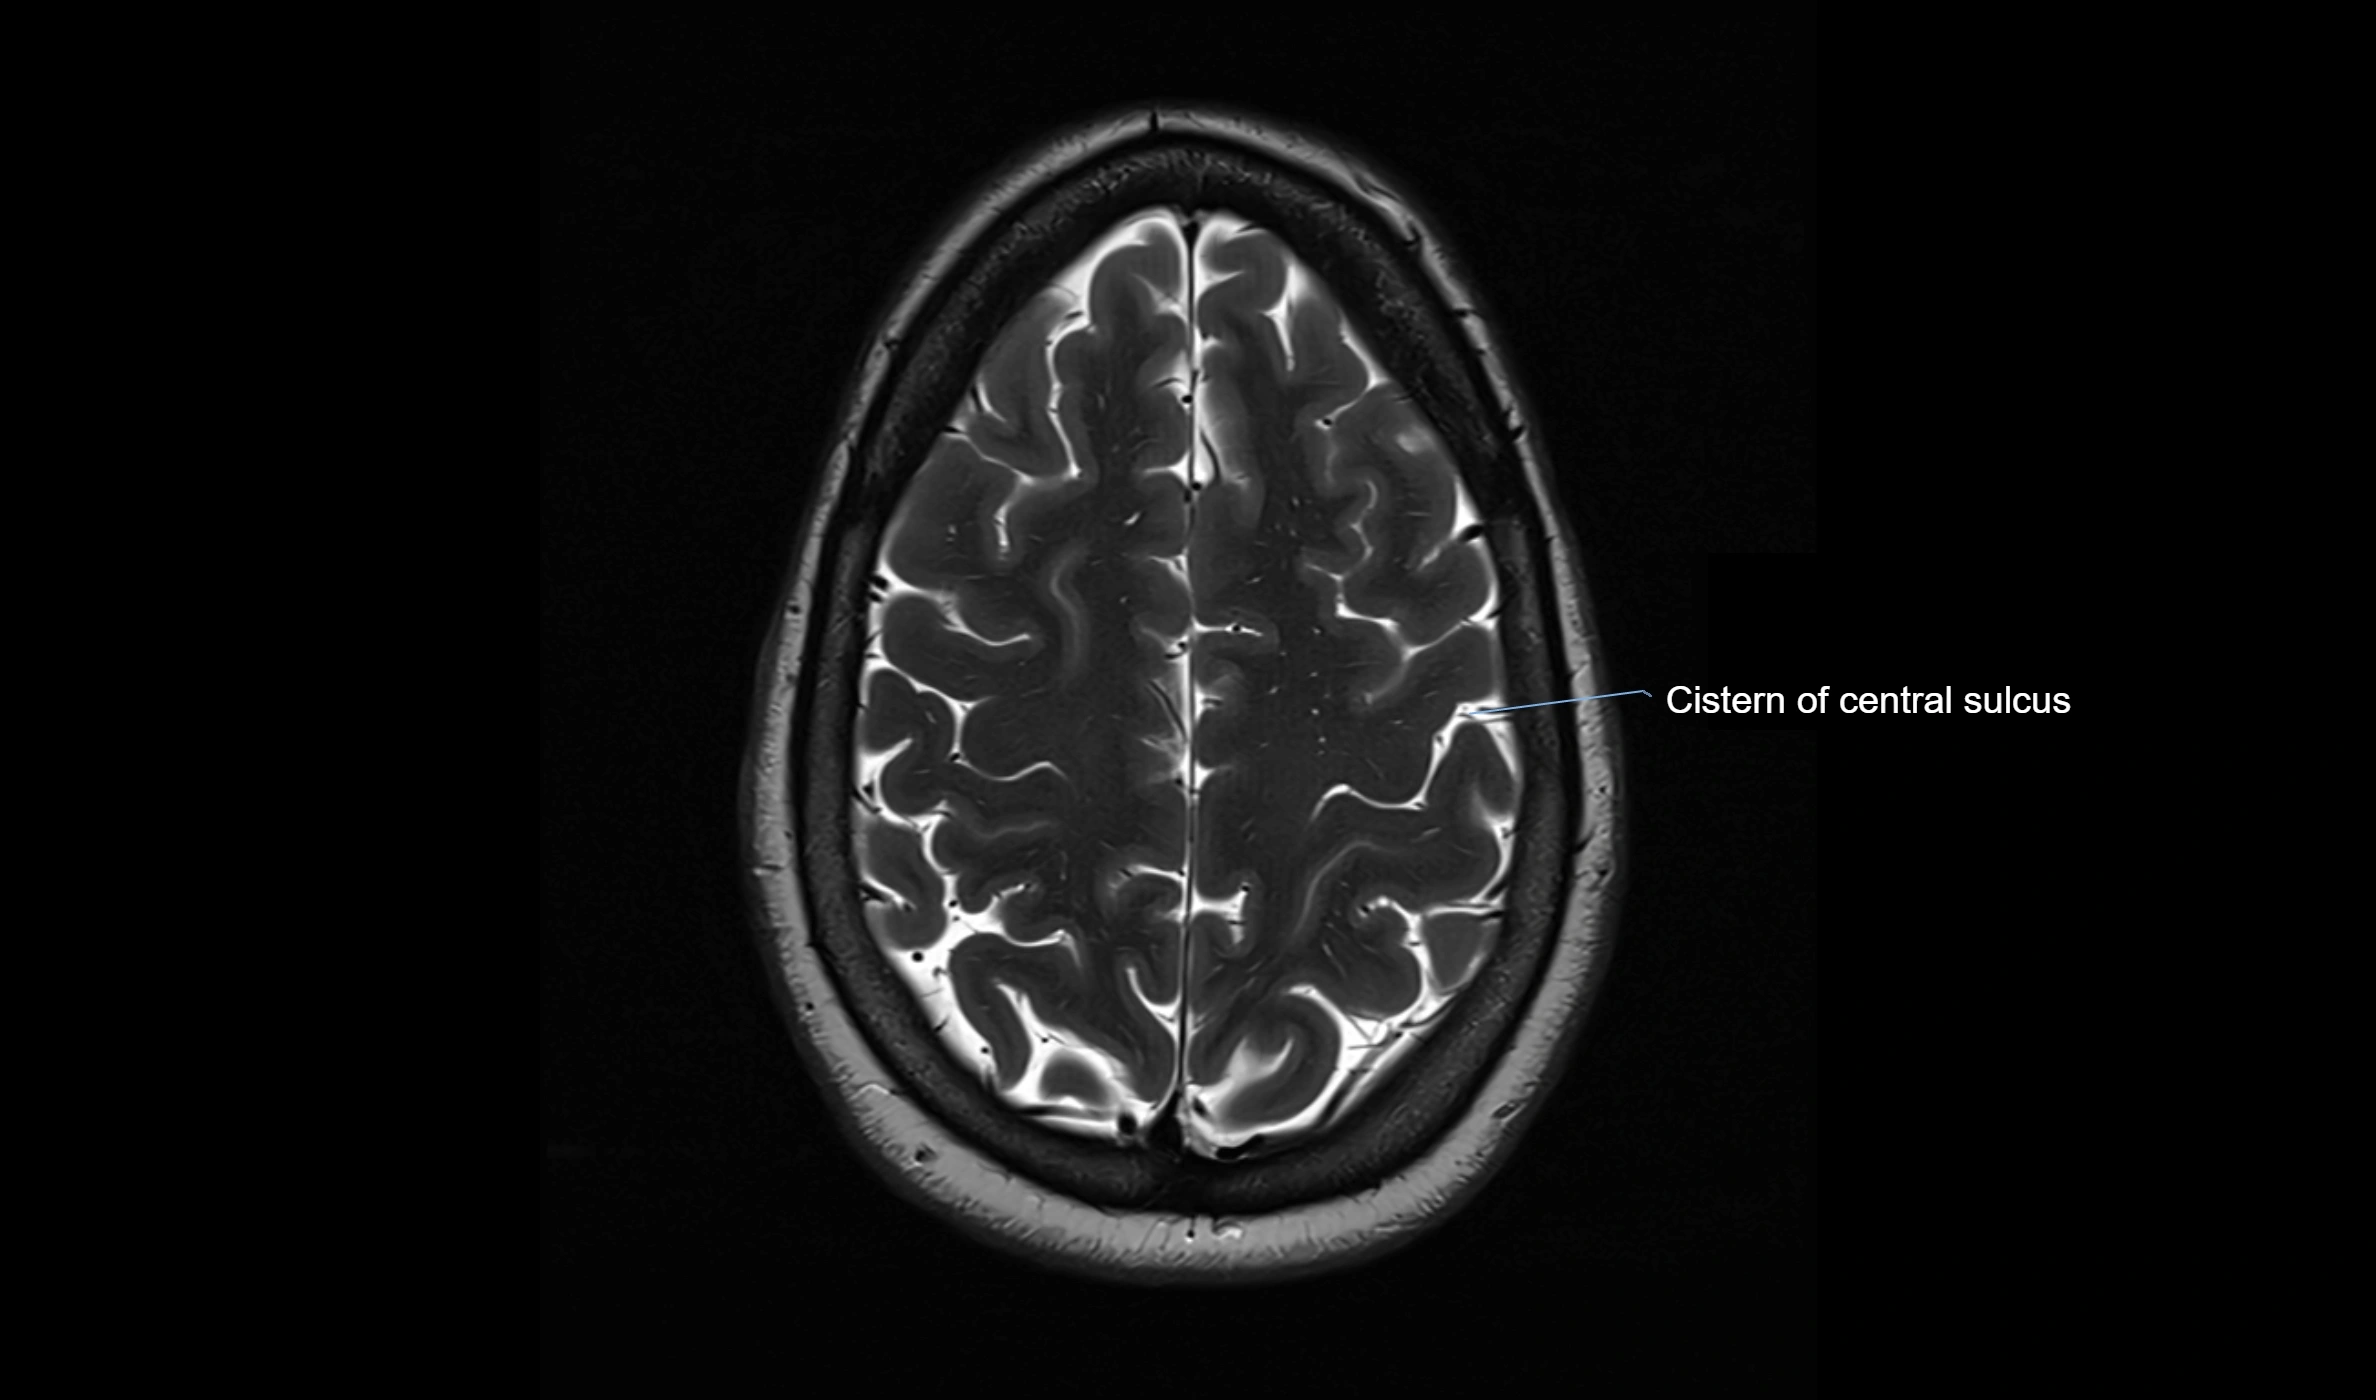

CT image

image